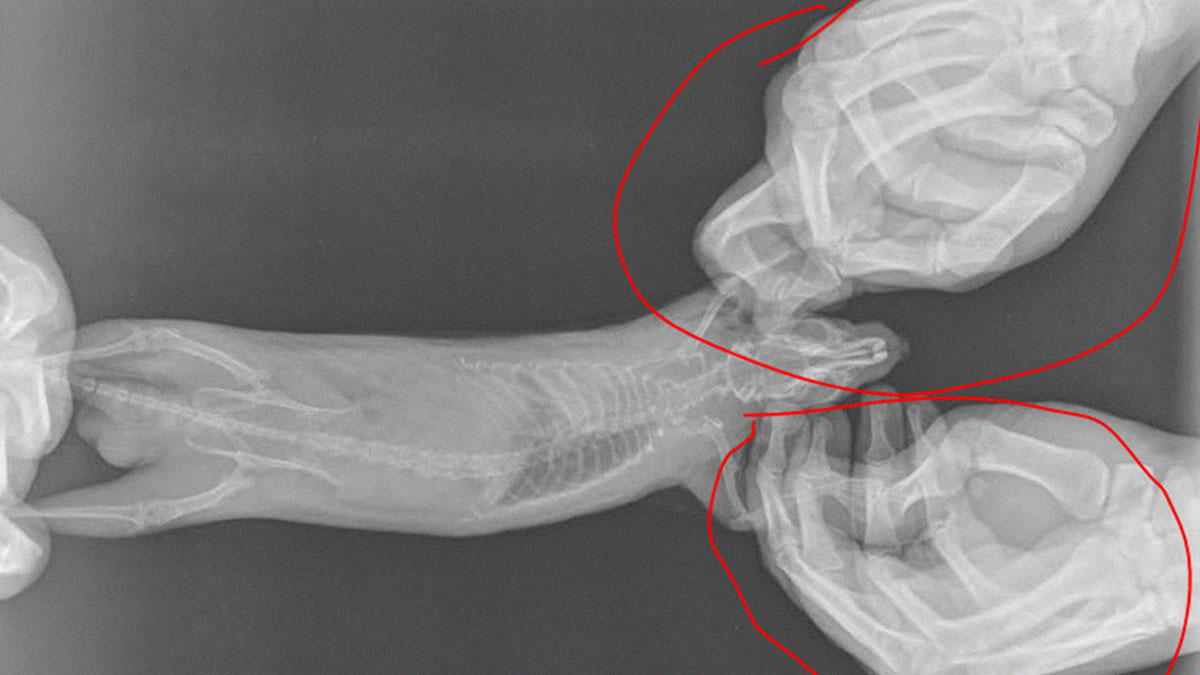

I Made X-Ray Of My Pet Rat Today And Accidentally Discovered That There Is Skeleton Inside Of Me